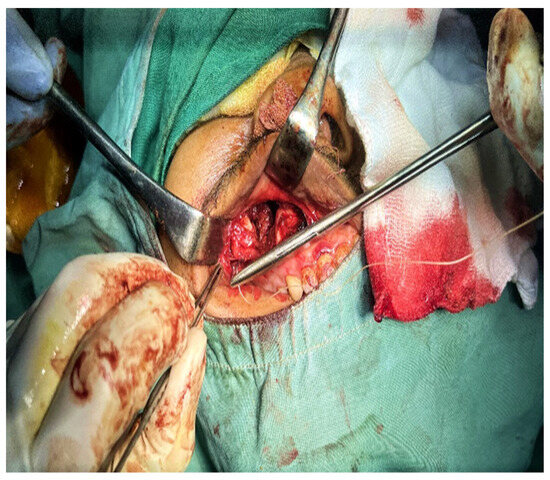

2. Case Presentation